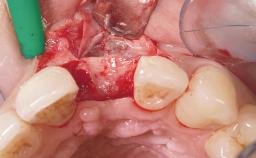

This 43-year-old male patient, a non-smoker, came to our practice because of a fracture of tooth 12 caused by a bicycle accident. Due to the combined para- and infrabony crown and root fracture, tooth extraction, and subsequent implant placement were suggested to the patient as the therapy of choice. The patient had high esthetic expectations with regard to the treatment outcome and asked for an immediate fixed provisional restoration. His individual esthetic risk profile summed up to a medium esthetic risk.

Placement Protocol Immediate implant placement

Tooth Site Maxillary incisor or canine

Socket Morphology Single-root socket

Socket Integrity Sufficient, with intact bone walls

Bone Volume Sufficient, with intact walls